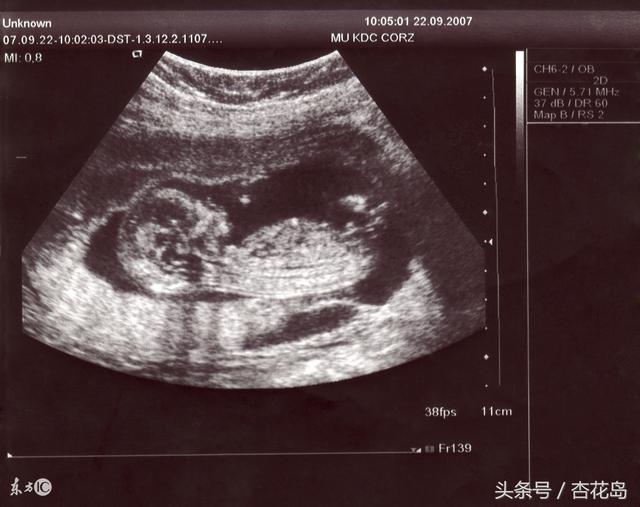

7、B超:早期确定胚胎着床及胚胎数/中期重点在排畸/晚期确定胎位及脐带状况等。

①孕早期6到8周时,B超主要检查宫内孕还是宫外孕,有几个胚胎(即几胞胎)以及确定孕周;以及时建档,另外要做较全面的常规检查:血常规、血型、尿常规、空腹血糖、肝肾功,艾滋、梅毒及乙肝的筛查等;

②孕中期11到13+6周时,胎儿的器官发育趋于完善,B超检查NT(即胎儿颈部透明带厚度),若>3mm唐氏儿可能性大;结合唐氏筛查的检查,可以提高对先天愚型的筛查检出率;此外继续补叶酸到怀孕3个月;

④孕18到24周,应该做系统筛查,排除六大畸形,推荐选择四维B超来筛查;检查宫颈管的长度进行宫颈评估;

⑥孕28到31+6周,B超检查宫颈长度、胎位,可能检出胎儿脑积水;

⑧孕37周以后,做B超判断胎位、入盆、羊水、胎盘成熟度等,若超过41周仍未生产,应住院、引产。